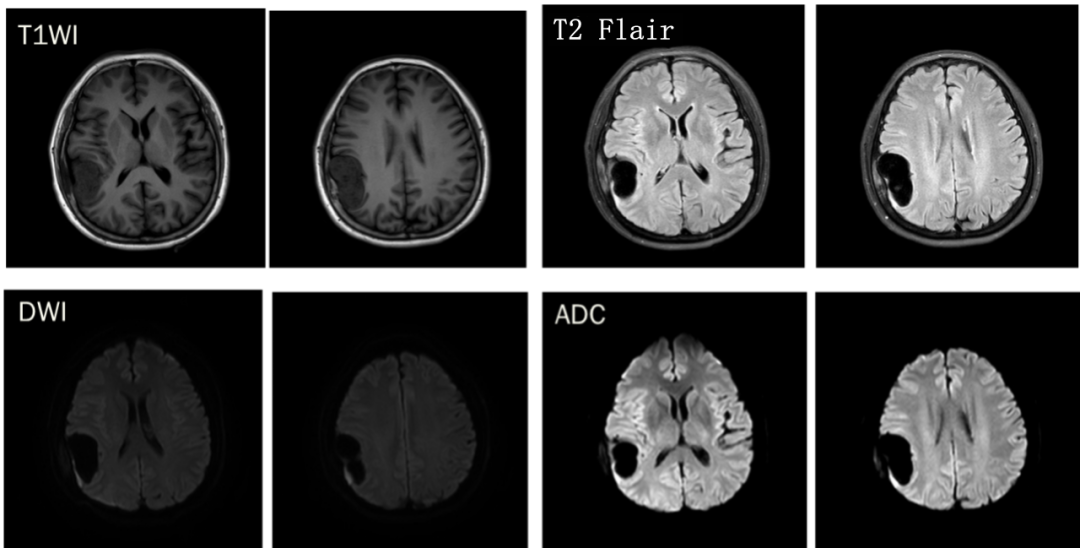

CASE 1

男,58 岁

CT 平扫:左侧额部占位,内伴钙化,周围见半片状水肿,大脑镰向右侧移位,邻近骨质未见破坏。

T1WI 呈等低信号,T2WI 实性成分呈等高信号,DWI 信号未见增高,ADC 值未见减低,增强实性成分明显强化,中央低信号钙化成分未见强化。邻近脑膜增厚(红箭头),脑膜尾征。

诊断:左侧额部脑膜瘤